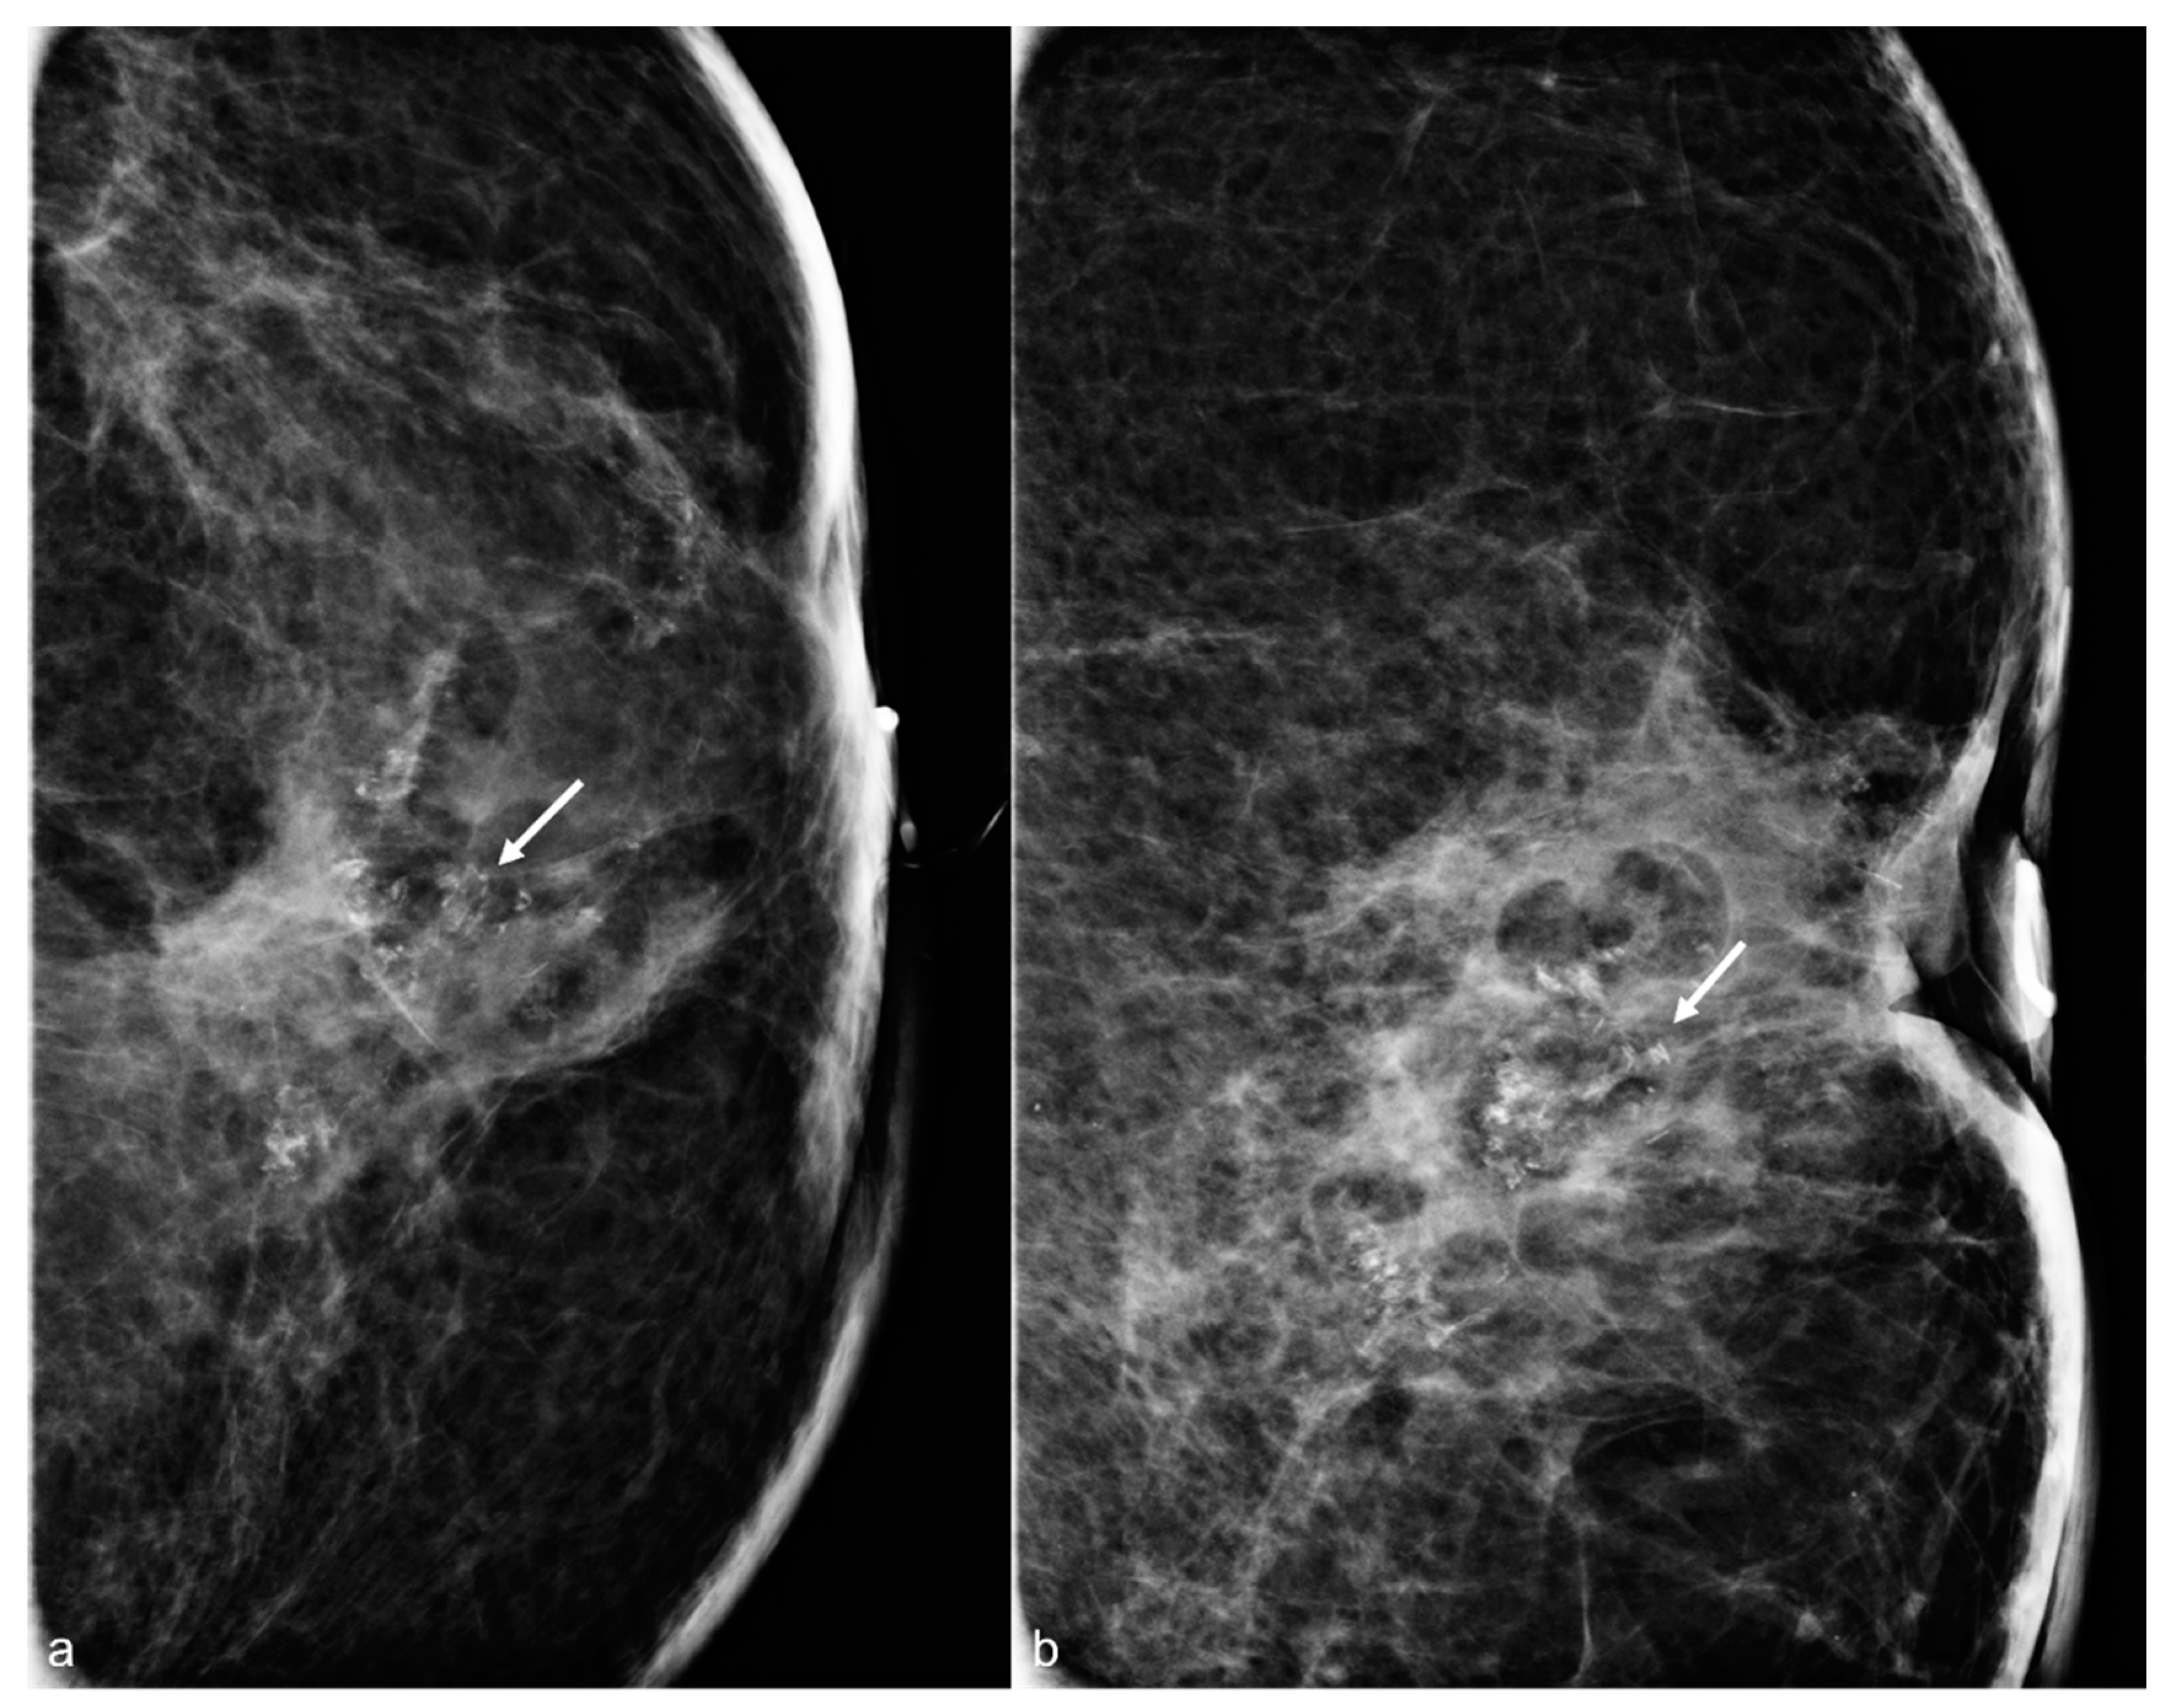

Figure 16. A 52-year-old woman with a history of subglandular silicone implants. Prior mammograms with implant displaced views were negative. A screening mammogram with bilateral CC and MLO views one year after BES (a) demonstrates a spiculated mass in the left lower inner quadrant (arrow), which was biopsied under ultrasound guidance with pathology revealing invasive ductal carcinoma. T1-weighted post-contrast MRI axial images demonstrate areas of fat necrosis in both breasts ((b,c), arrowheads). An enhancing mass with a biopsy clip is seen adjacent to the surgical scar ((c), arrow) in the left breast representing the biopsy proven carcinoma.